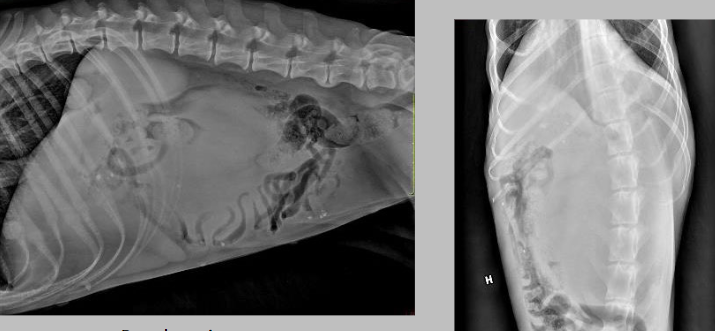

what is going on here?

there is one tiny kidney and one huge kidney: compensatory hypertrophy